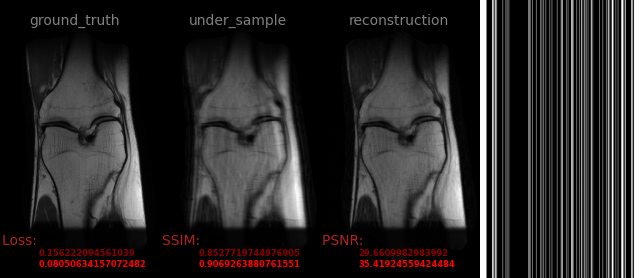

110.png